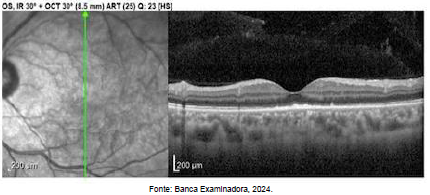

Paciente, sexo masculino, 20 anos, comparece ao servico de oftalmologia com queixa de baixa acuidade visual no olho esquerdo, com 3 dias de evolução. Nega sintomas associados. Paciente desconhece comorbidades prévias e nega uso de medicamentos. Ao exame, apresenta acuidade visual no OE 20/100 e presença de lesões sub-retinianas amarelo-pálidas. OD sem alterações ao exame. Imagens do OCT do paciente abaixo.

Durante propedêutica laboratorial, o paciente mostrou-se reagente à sorologia específica para uma doença. Qual doença sistêmica provavelmente o paciente apresenta que poderia levar a esse acometimento oftalmológico?